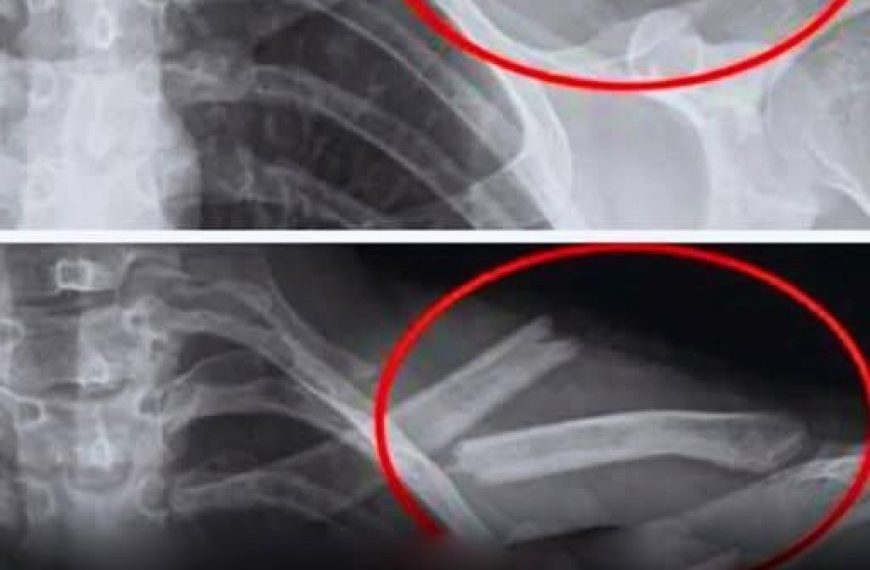

Studien zeigen, dass übermäßiger Limonadenkonsum mit einer Verringerung der Knochendichte einhergeht, insbesondere bei Frauen. Mit anderen Worten: Ihre Knochenwerden brüchiger … manchmal ohne jegliche Symptome, bis es zu einem Bruch kommt.

Eine US-Studie mit 2.500 Frauen ergab, dass diejenigen, die regelmäßig Cola konsumierten, eine geringere Knochendichte in den Hüften hatten. Und dies, ohne dass man sich dessen bewusst ist.

Eine an heranwachsenden Mädchen durchgeführte Studie hat außerdem einen Zusammenhang zwischen dem Konsum von Limonade und einem erhöhten Risiko für Knochenbrüche gezeigt.